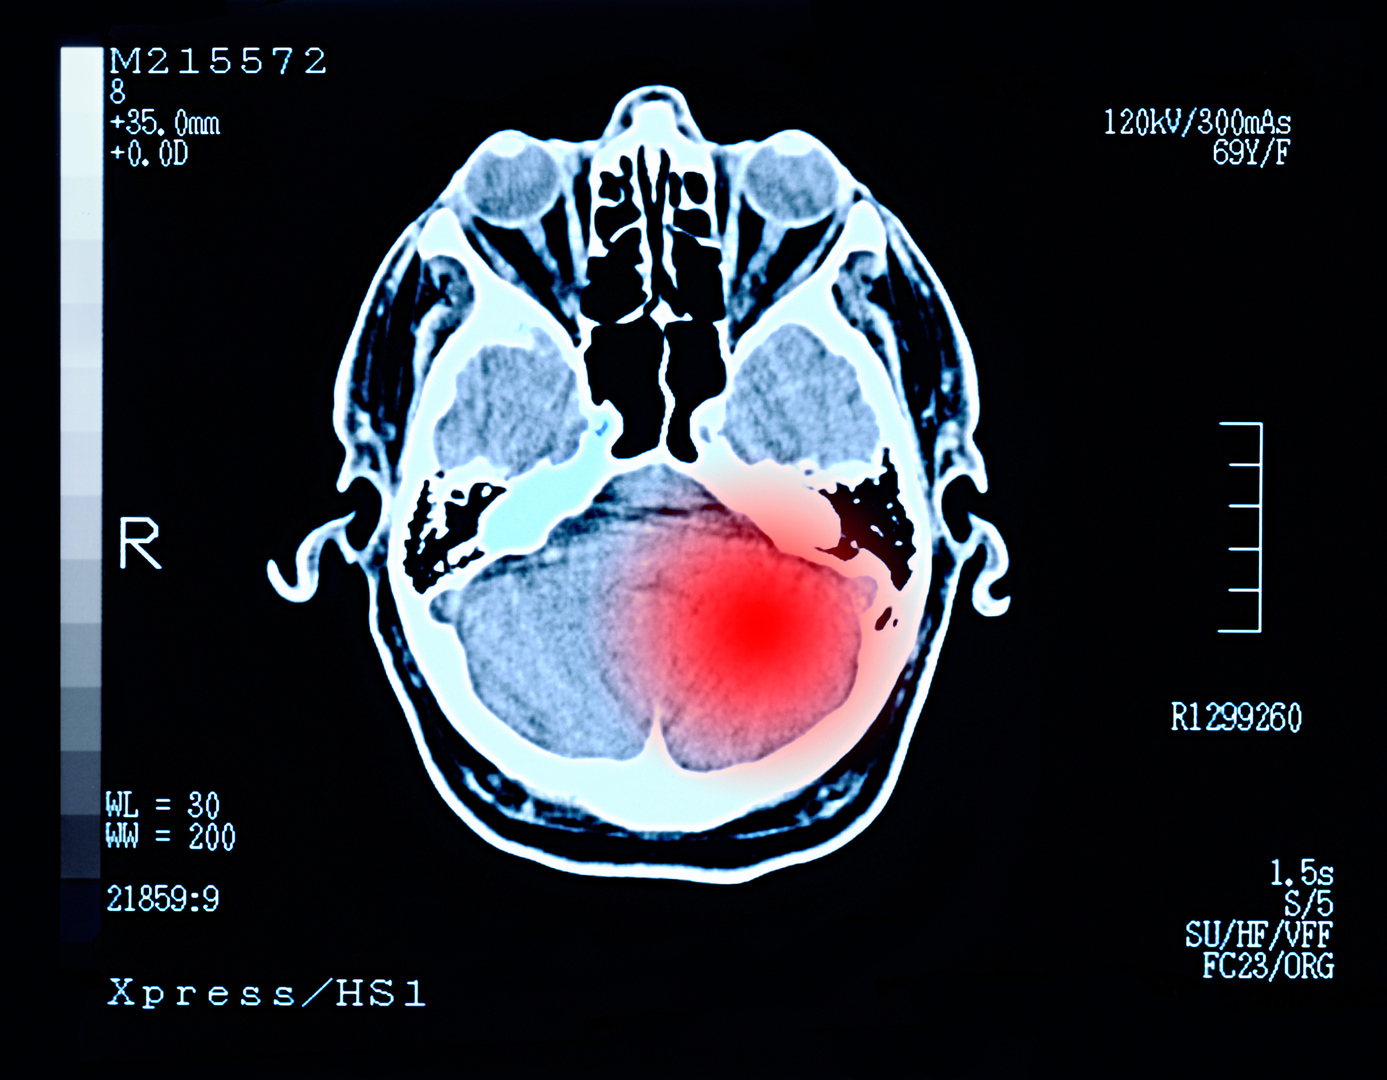

أمراض عيون شائعة بعد سن الخمسين

يحذر الدكتور قسطنطين روسكوف أخصائي طب وجراحة العيون من زيادة خطر الإصابة بأربعة أمراض عيون لدى الأشخاص فوق سن الخمسين.

ووفقا له، بعد سن الخمسين، يزداد خطر الإصابة بإعتام القرنية، ما يصعب على الشخص القراءة عن قرب. كما يزداد خطر الإصابة بمرض التنكس البقعي المرتبط بالعمر، وهو عملية مرضية في الجزء المركزي من الشبكية المسؤول عن حدة البصر.